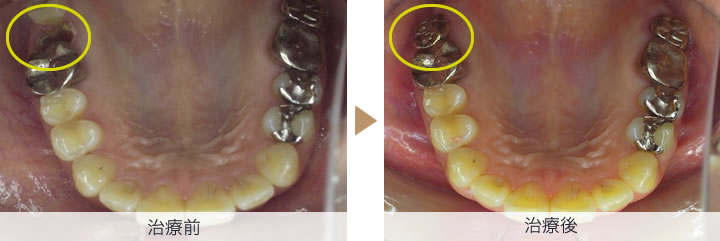

残せない歯を抜歯、さらに親知らずを抜歯し保存します。すぐに抜歯した親知らずを残せない歯を抜歯した部分に移植します

一週間後に抜糸し移植歯がある程度固定され歯肉が治癒してきたら、根管治療をします。その後、4か月ほど移植歯が骨とくっつき安定するまで待ち仮歯を入れ様子をみます。

移植した歯が安定したので、被せ物を装着し、治療完了となります。

治療後のレントゲン写真にて、移植歯の周りに骨ができており、移植が問題なく成功していることがわかります。